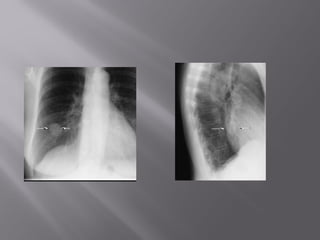

 7. Rotation

 Medial ends of

bilateral clavicles are

equidistant from the

midline or vertebral

bodies

If spinous process appears closer to the right clavicle (red arrow),

the patient is rotated toward their own left side

If spinous process appears closer to the left clavicle (red arrow),

the patient is rotated toward their own right side

 7. Rotation Medial ends of bilateral clavicles are equidistant from the midline or vertebral bodies

If spinous processappears closer to the right clavicle (red arrow), the patient is rotated toward their own left side If spinous process appears closer to the left clavicle (red arrow), the patient is rotated toward their own right side